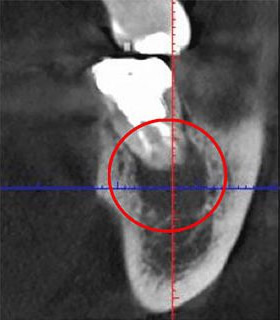

こちらの画像で「根管」をご覧ください。歯の内部に見える黒い筋が、根管と呼ばれる部分です。

根管は非常に複雑な形状をしており、最も狭い部分では直径が1mmにも満たないことがあります。このような細い根管から細菌感染した組織を完全に取り除くのは、非常に難しい作業です。

しかしながら、日本の多くの歯科医院では、このような精密な作業を肉眼で行っており、これが日本における根管治療の成功率が低い一因となっています。

私たちは、歯科専用の顕微鏡である「マイクロスコープ」や「高倍率ルーペ」を活用し、視野を大きく拡大した状態で治療を行っています。